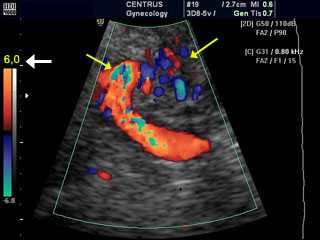

Теоретически в любую полость тела, к которой обеспечивается доступ УЗ датчика, можно ввести контрастное вещество. Самым успешным применением в этой категории является контрастная гистеросальпингосонография (HyCoSy, введение контраста в полость матки) для оценки проходимости маточных труб (поиск причин бесплодия).

Немецкие ученые сообщили о результатах исследования, в котором приняли участие пациентки с расстройствами детородной функции, прошедшие трансвагинальное УЗИ и гистеросальпингосонографию с УЗ контрастом. Результаты гистеросальпингосонографии сравнили с результатами более инвазивных устоявшихся методов, таких как хромолапароскопия, и обнаружили соответствие 91%.

Гистеросальпингосонография быстро становится предпочтительным скрининговым методом определения проходимости маточных труб.